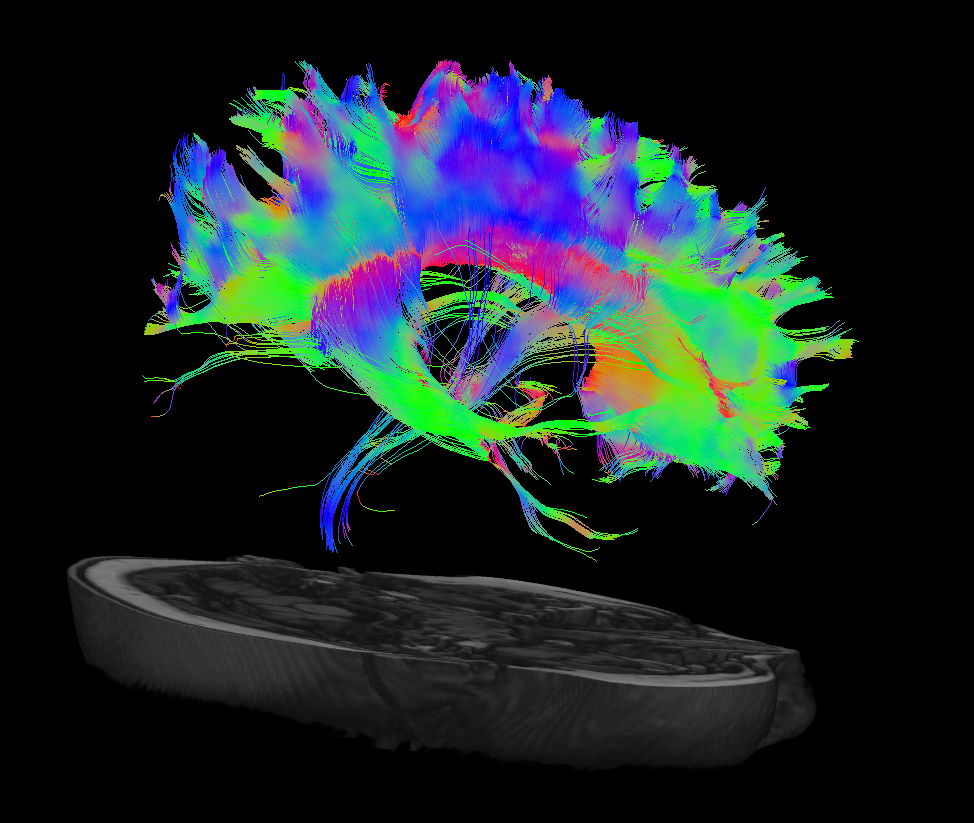

Structural connectivity

White-matter is typically associated with the structural connectivity within the brain. One of the best ways to understand white-matter in the brain is through using diffusion-weighted MRI by tracking the diffusion of water within the brain across time. The diffusion of water present in the brain tends to be restricted by larger macromolecules such as myelin, axon bundles, microtubules, etc., which we can use to identify structural connections. We can then model this restriction to recreate specific tracts (i.e. tractography), such as the corticospinal tract (motor) or dorsal column medial lemniscal (sensory) tract.

Our research focuses on how structural connectivity changes following a perinatal stroke. Since the main disability in perinatal stroke is a lifelong motor disability, we are interested in how the motor system connectivity develops following such strokes. We can isolate certain tracts that we know are involved in motor outcomes (corticospinal tracts, cerebellar tracts, etc.) and assess potential relationships of such tracts with their motor function. Our primary goal is to develop potential biomarkers of clinical outcomes using this modality of imaging.